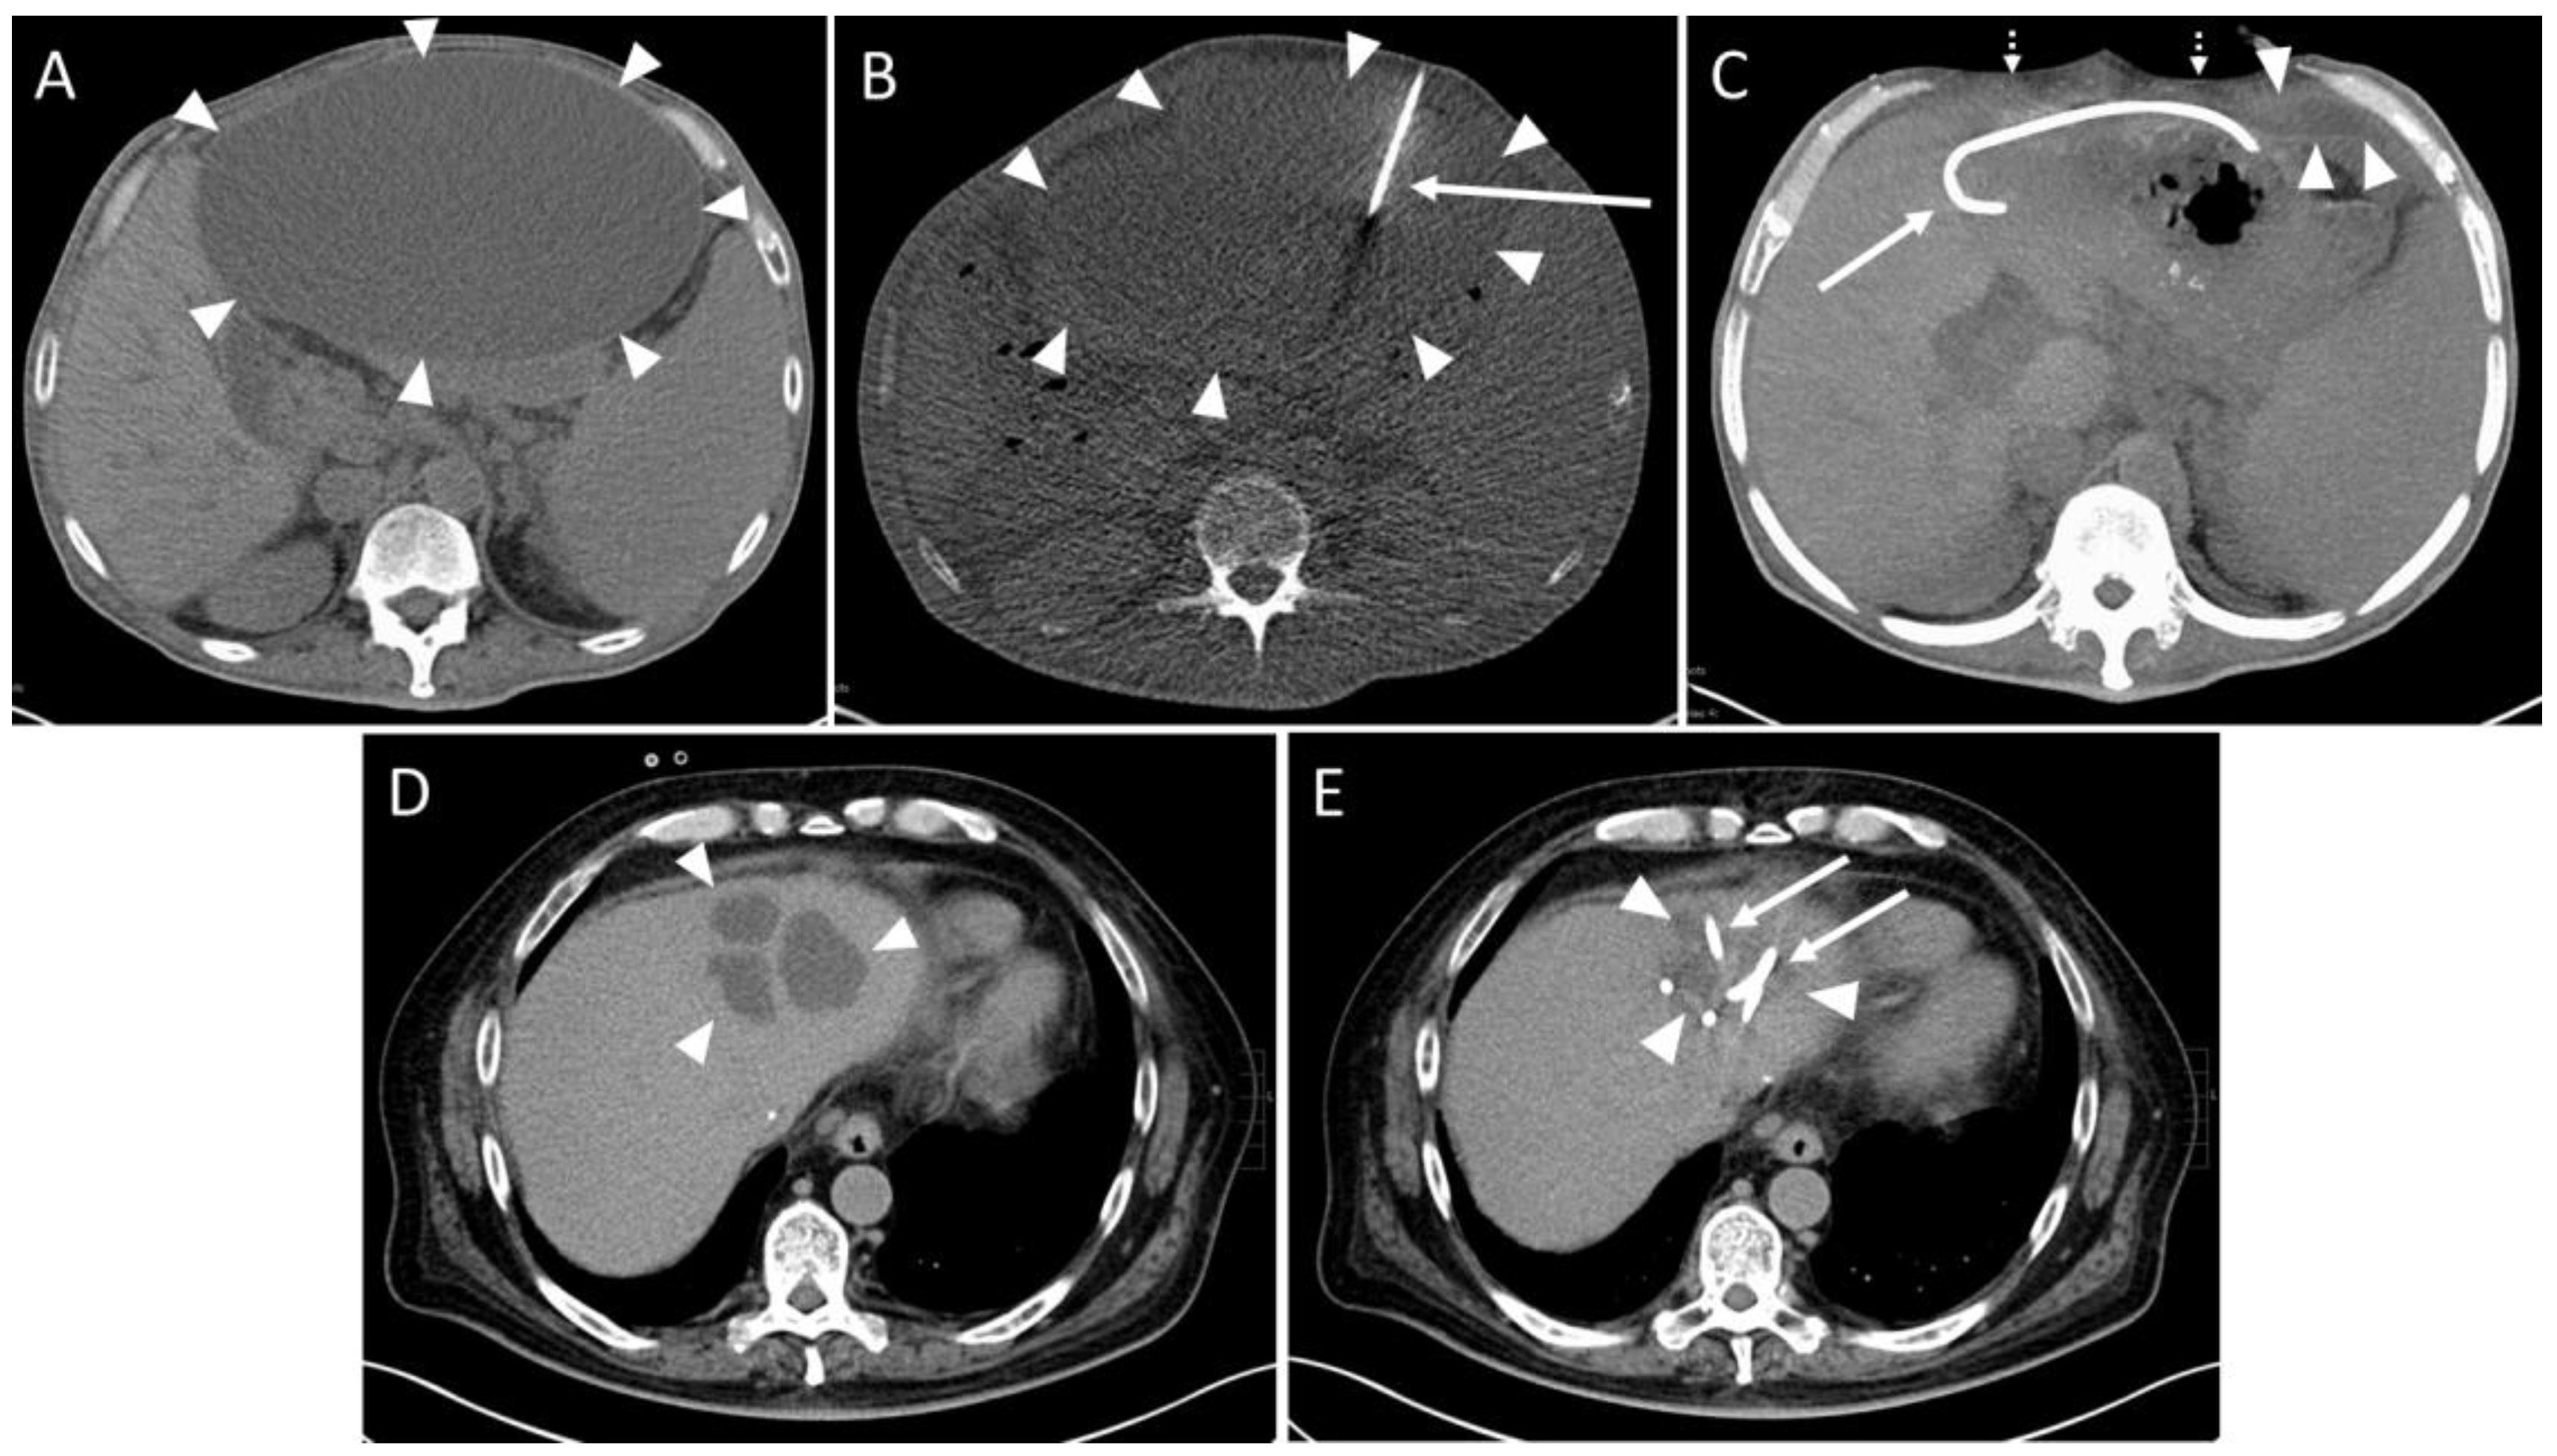

Figure 3. Example of a CT-guided drainage placement involving minor complications in accordance with SIR (Society of Interventional Radiology) guidelines. A 30-year-old female with a history of liver transplantation due to primary sclerosing cholangitis. Postoperative ultrasound follow-up revealed a cystic subhepatic fluid collection that recurred over months and was considered to be a biloma. The patient was symptom-free. However, approximately 10 months after transplantation the patient complained of increasing feeling of pressure and pain in the right lower quadrant of the abdomen. (A) MRI scan (coronary reconstruction) revealed a roundish thin-walled fluid collection (asterisk) in the subhepatic paracolic gutter, which, in the context of the described symptoms, was an indication for elective CTD. Additionally, note the small amount of ascites in the perihepatic and perisplenic gutter (dotted arrow). (B) Pre-interventional CT planning scan shows the cystic fluid collection (asterisk) and the surrounding ascites (dotted arrow). (C) Post-interventional control scan: Due to a highly rigid wall an 8F drain (solid arrow) could only partially be inserted via the Seldinger technique. The proximal end is dislocated in the right subhepatic gutter (dotted arrow). (D) Post-interventional unenhanced CT control scan after partial aspiration and removal of the drain exhibits a small hemorrhage (dashed arrows, density: 22 Hounsfield units) at the bottom of the cavity of the cystic formation (asterisk). Further, a slight increase in the extent of the fluid collection (dotted arrow, compare to figure (B)) in the gutter was observed, most probably due to fluid loss through the drain access hole into the gutter. Microbiological analysis was negative. (E) CT fluoroscopy: After 4 weeks, a new approach using the Trocar technique was attempted and a successful drainage placement was obtained. Asterisk: cystic fluid collection. Arrow: 8F drain. However, 6 months later, due to recurrence of the fluid-filled collection with vena cava compression, the formation was operatively resected. Histopathological examination revealed a cholangiocele of the bile duct system. (F) Postoperative MRI scan 4 month after surgery shows only parts of colon and small amounts of ascites subhepatically (dotted arrow) at the original site of the cholangiocele.